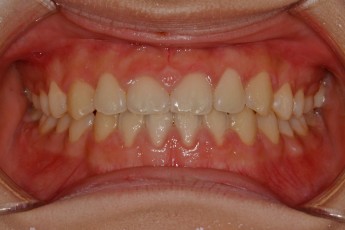

BEFORE & AFTER